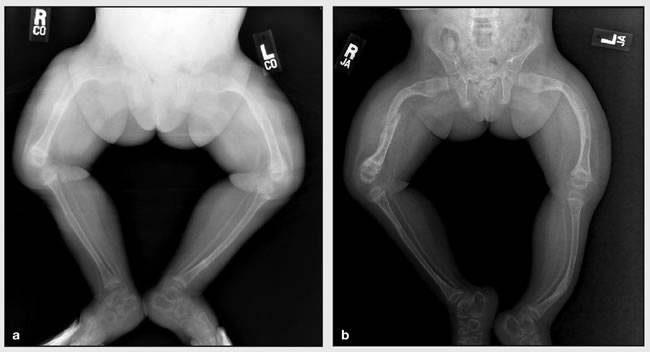

Наиболее распространенными являются травмы длинных костей — берцовой, бедренной, плечевой. Они могут возникать еще в период внутриутробного развития, в процессе прохождения по родовым путям или в первые месяцы жизни. При рождении часто происходят переломы ключиц, конечностей. Особенно часто это случается при использовании вспомогательных акушерских устройств, например, щипцов. При неправильном сращении кость деформируется, наблюдаются патологические изменения в грудной клетке и позвоночнике, которые можно увидеть на фото. Кости черепа размягчаются.

- При 2 наблюдаются выраженные нарушения в формировании скелета: деформация и укорочение костей, образование остеофитов. Ребенок сильно отстает в развитии.

Ренгенологические признаки зависят от степени тяжести патологического процесса. Отмечаются истончение верхнего слоя длинных костей, уменьшение объема тканей, патологические переломы с формированием костных мозолей. Кости черепа у ребенка размягчены, швы между ним зарастают длительное время.

Хирургические вмешательства показаны при тяжелых формах болезни Вролика, сопровождающихся выраженной деформацией костей. Операция подразумевает рассечение измененного участка с целью восстановления правильной формы.

Далее выполняется остеосинтез — сопоставление отломков с помощью фиксирующих приспособлений.